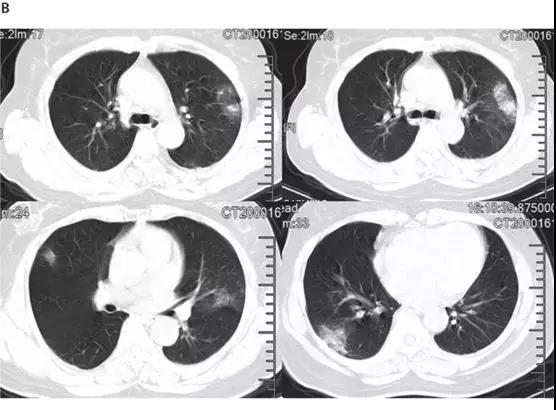

非ICU患者的代表性胸部CT检查表现为双侧毛玻璃样混浊和亚段实变(见下图)。